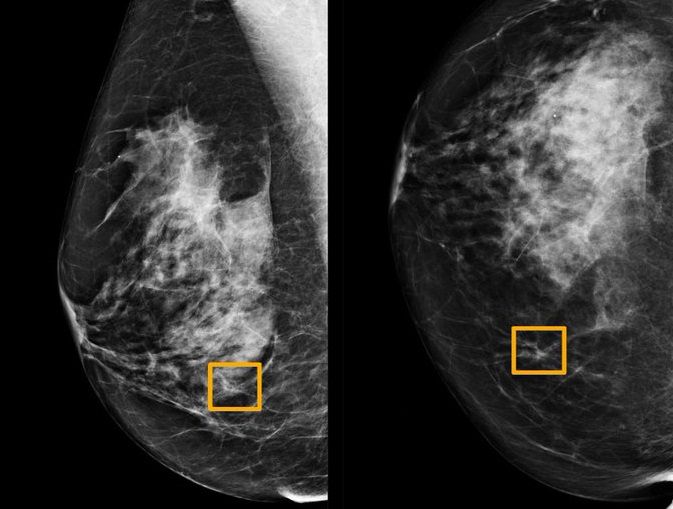

Un programa informático mostró una mejor precisión que los expertos [...]